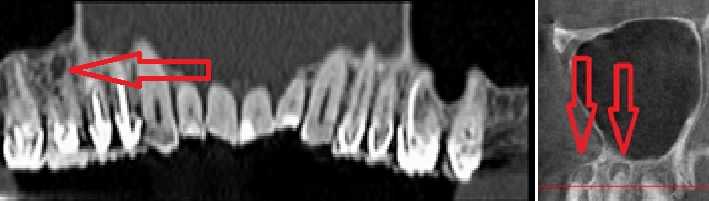

Стрелками показаны фрагменты пломбировочного материала (вид спереди и сбоку), который при пломбировании канала выпал за пределы зуба и «упёрся» в область залегания ветви тройничного нерва. У пациента долго болел зуб после лечения пульпита, затем онемела верхняя губа и часть щеки.

Стрелками показаны кисты корней зубов (вид спереди). Кисты в данном случае представляют собой замкнутые очаги инфекционного воспаления. Киста со временем набухает и создает давление на ветви тройничного нерва, отсюда онемение лица и боль. Осложнение после лечения пульпита.